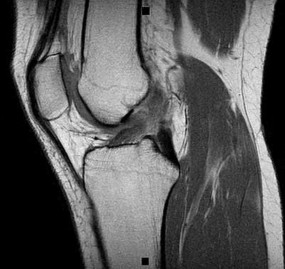

A 22-year-old man sustains an injury to his right knee in a motor vehicle collision. Figure 22a is the posterior stress radiograph of the involved knee, and Figure 22b is a selected MR image that identifies the injured structure.

CLINICAL SITUATION FOR QUESTIONS 22 THROUGH 25

The stress radiographs demonstrate posterior instability of the right knee in flexion. The MR images demonstrate injury to both the anterior and posterior cruciate ligament (PCL), with the stump identified with the arrow on the MR image (Figure 22b). The PCL has 2 functional bands. The anterolateral bundle originates from the roof of the intercondylar notch. It runs in a posterolateral direction onto the tibial crest between the posterior attachment of the medial and lateral menisci. During a double-bundled posterior ligament reconstruction, the

anterolateral bundle is tensioned with the knee in a position of mid flexion. The posteromedial bundle has a variable pattern of tension both in extension and in high flexion. Tensioning of the posteromedial bundle in extension may contribute to resistance against knee hyperextension.

The meniscofemoral ligaments are variably present. Although 93% of knees have been reported to have at least 1 meniscofemoral ligament present, both ligaments are simultaneously present in approximately 50% of knees. The ligament of Humphrey (anterior meniscofemoral ligament) and ligament of Wrisberg (posterior meniscofemoral ligament) are delineated by their anatomic relationship to the posterior cruciate.